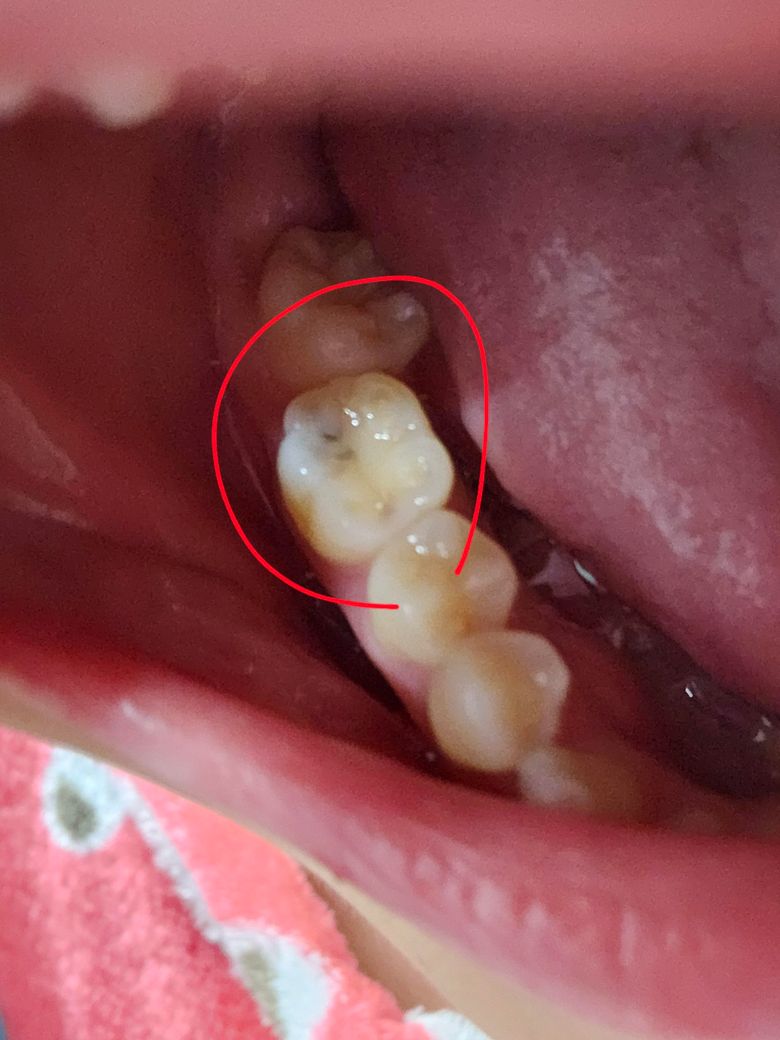

5일전에 치과에 방문했었는데 파노라마 찍었거든요. 그때 충치는 없다고 하셨는데 우연히 오늘 양치하다가 왼쪽 아랫 어금니에 충치로 의심되는 어금니를 발견했습니다..

이럴수가 있나요?

정지된 충치일 수도 있나요?

• 1번 째 사진

정확한건 엑스레이를 찍어보셔야되겟지만, 안쪽으로 충치가 진행중인거 같습니다. 단기간에 충치가 생긴건 아니고 그전부터 충치가 잇엇을 가능성이 높습니다.

충치는 단기간에 진행되지는 않습니다. 5일 전에 치과 검진에서 충치가 없다고 했다면, 갑자기 충치가 생겼다고 보기 어려우며, 이미 발생했지만 진행이 멈춘 상태일 가능성이 높습니다.

얕은 충치인 경우 파노라마 사진으로는 드러나지 않을 수도 있습니다. 정확한 검진을 위해서는 파노라마 찍고 의심되는 치아 먼저 체크한 뒤 그 다음에 전체적으로 육안으로 살펴보고, 기구로 긁어본 뒤 또 의심되는 치아에 대해 좀 더 해상도 높은 작은사진(치근단사진)을 찍어보는 것이 정석입니다. 처음에 파노라마 사진 찍는 건 전체적으로 상태를 보기 위함이고 치아 외에도 턱관절, 상악동 등 주변 구조물도 확인합니다.

충치는 5일만에 생기지 않습니다 상황에 따라 다를지만 보통 1달이상 지나면서 생기는 경우가 많습니다. 사진으로 이는 충치는 내부에 있는 충치로 안에 이물질이 들어가게 되면 나오지 않아서 진행될수 있을것으로 생각됩니다.